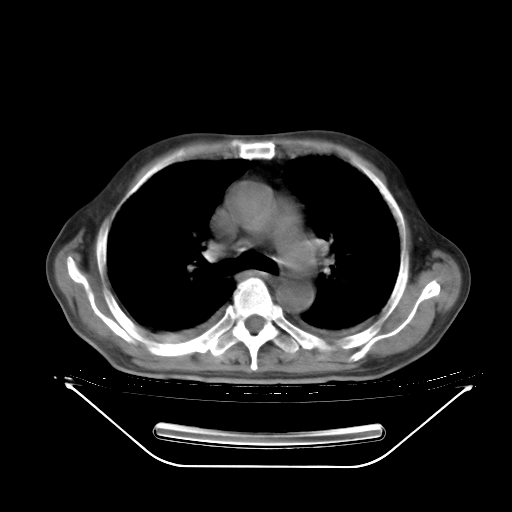

5月9日肺部CT(在4月27日齐鲁医院肺部CT描述部分肺组织磨玻璃样改变,12天后肺组织广泛磨玻璃样改变)

2009年5月9日肺部CT

大致读了系列胸部CT:纵隔窗无明显异常,肺窗:从4、27至今:主要是双肺中下野外带可见毛玻璃样改变,目前处于急性肺泡炎阶段,至于原因考虑1、结替组织或胶原血管性疾病所致?2、恶性疾病如恶组在肺部所致的表现或细支气管肺泡癌?3、药物或其它原因如肺蛋白沉着症所致肺泡炎目前不太可能?总之,明天就去请我院的呼吸科、感染科、血液科和临免专家会诊哈。